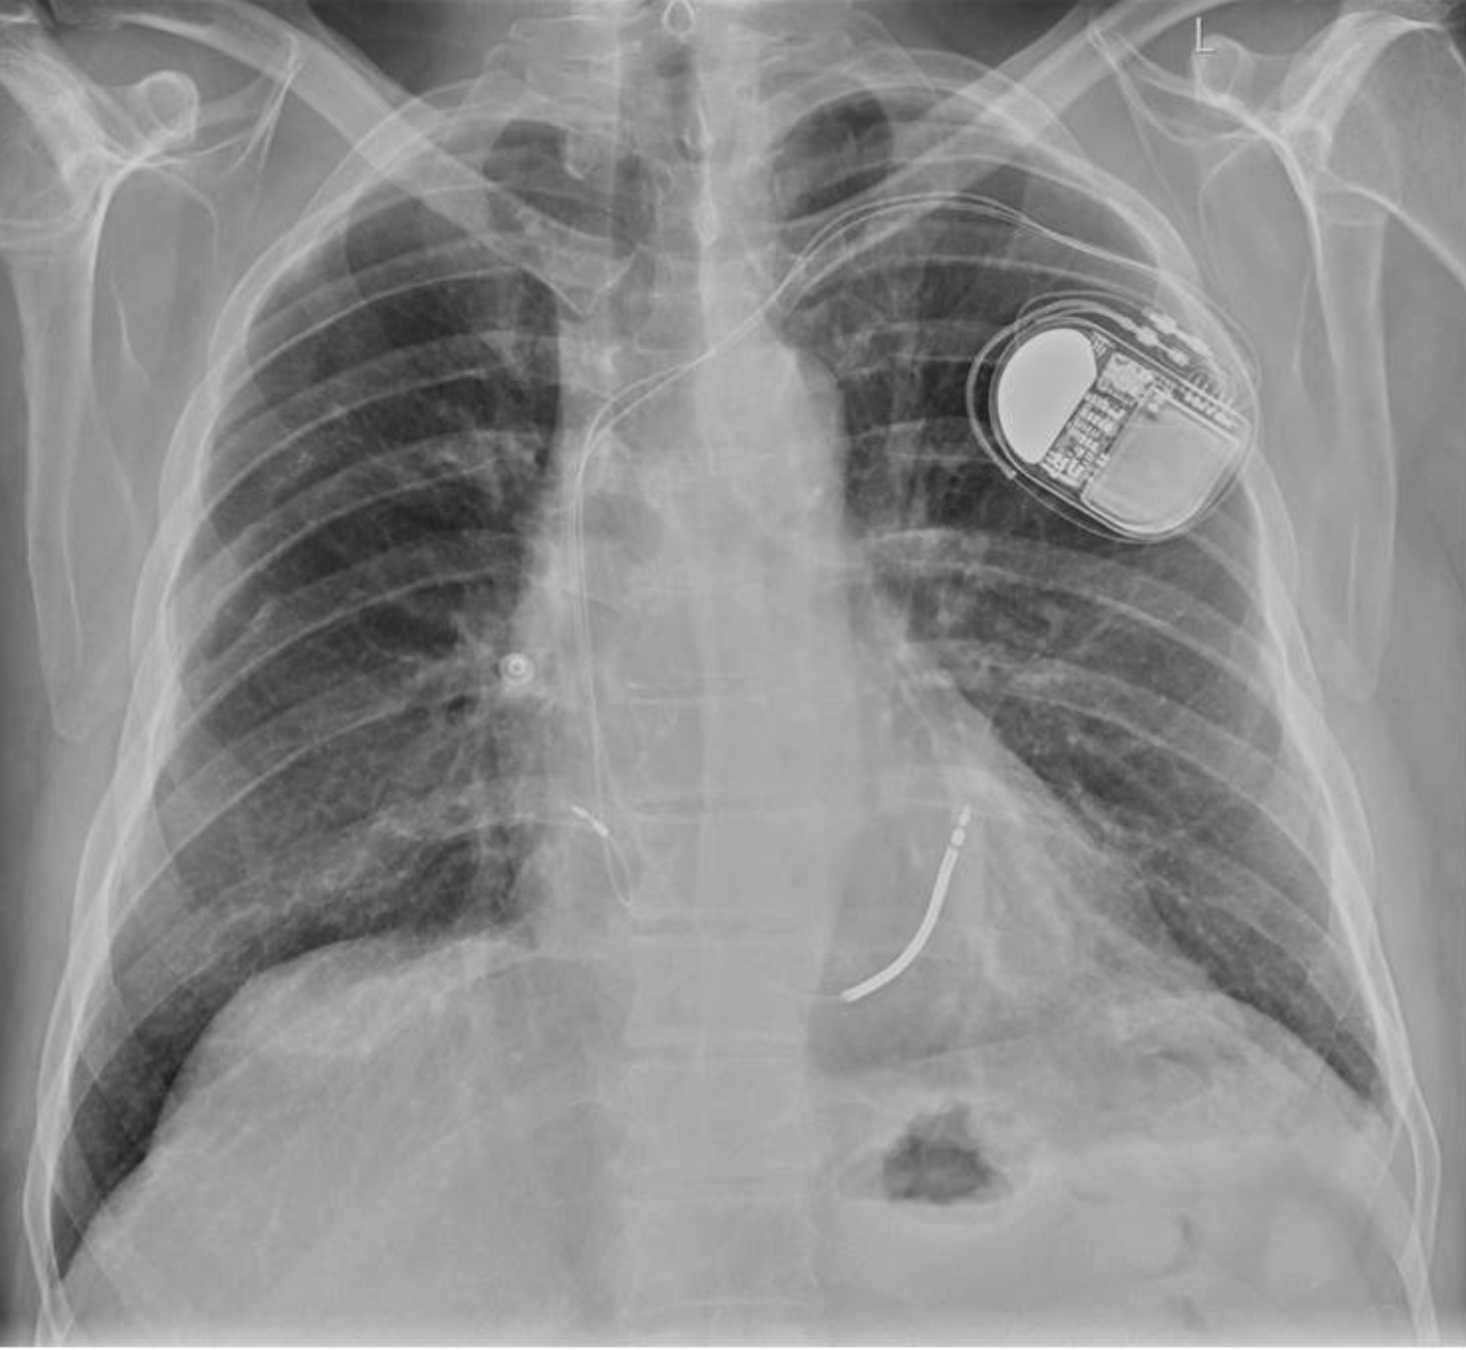

CORRECT NG PLACEMENT

INCORRECT NG PLACEMENT